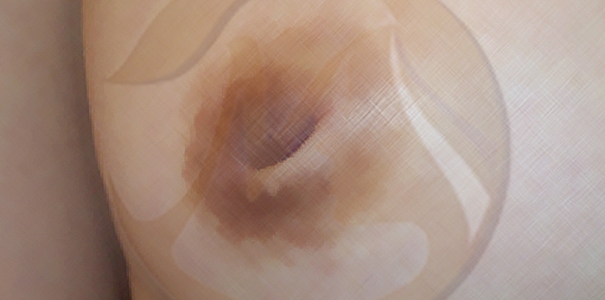

2단계

1단계에 비해 당기는 것이 쉽지 않고 바로 다시 함몰됨 -